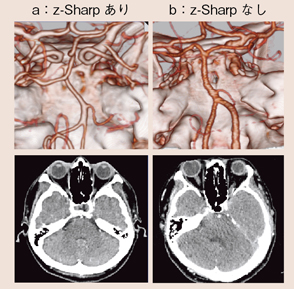

図9に,z-Sharpの有無による頭部の画像を示す。Windmillアーチファクトは,アキシャル画像で風車状に現れ,コロナルやサジタルでは,筋状になることが画像の異質感を生む。z-Sharpによりどの方向からでも同一の画質感で観察することができ,解像度の高いボリュームデータを得ることができる。これは,3D画像でも同様である(図10)。ボリュームデータを幅の広い照射野によって得ようとすると,X線ビーム幅が広がることにより,散乱線の影響や,線束中心と辺縁の空間分解能の違い,ヒール効果の影響による画像の劣化が表れてしまう。照射野を広げ過ぎずz-Sharpを用いることで,すべての位置において安定した高いボリュームデータを得ることができる。

図10 頭部CTAにおけるWindmillアーチファクトの影響